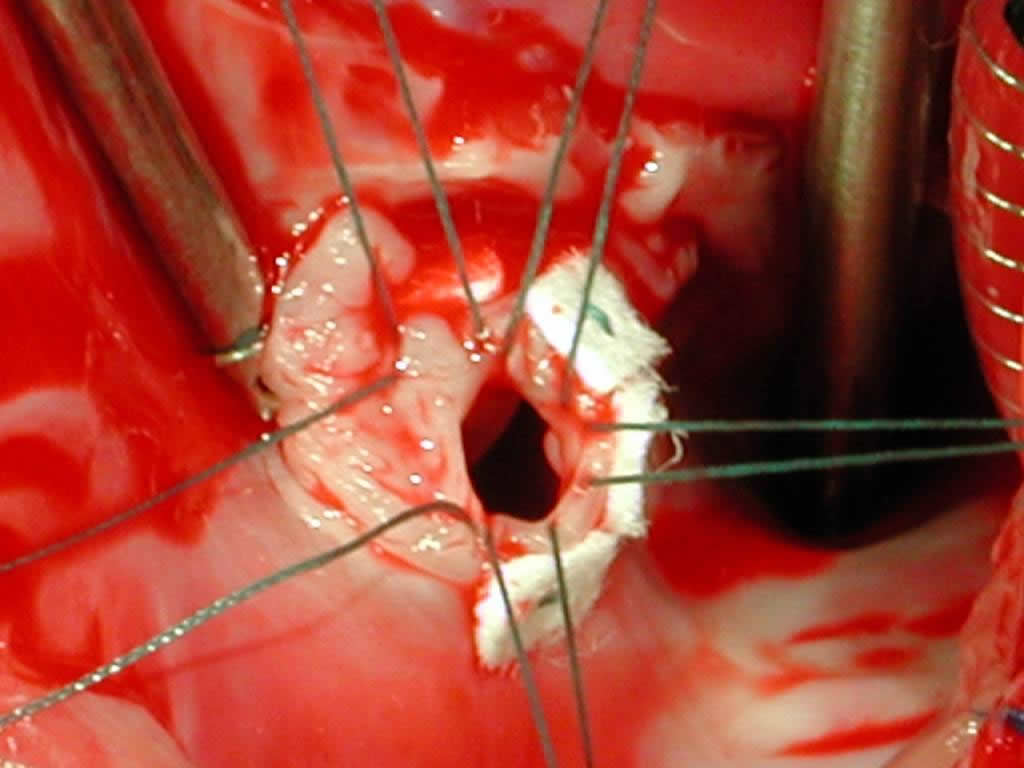

Figure 12 shows a 0.4-mm thickness Gore-Tex® cardiovascular patch in which sutures have been placed, lowered into the field.

Figure 13 shows the completed repair with the tricuspid valve again filled with saline and demonstrating that the tricuspid valve is competent.